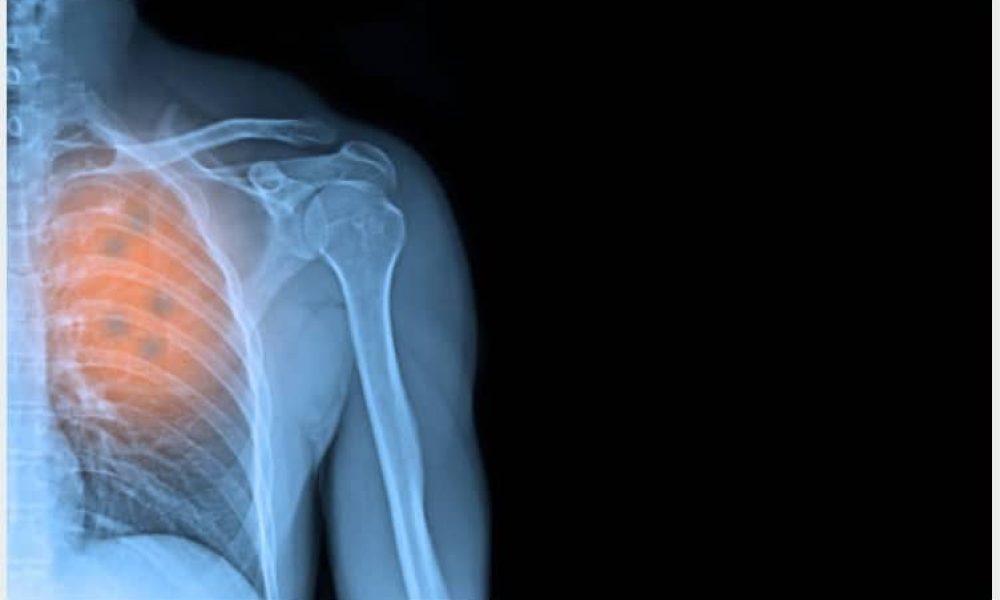

Ainsi, le ministère de la Santé et des Services sociaux (MSSS) annonce la mise sur pied d’un projet de trois ans pour dépister le cancer du poumon.

C’est prévu via la technique d’imagerie par résonance magnétique.